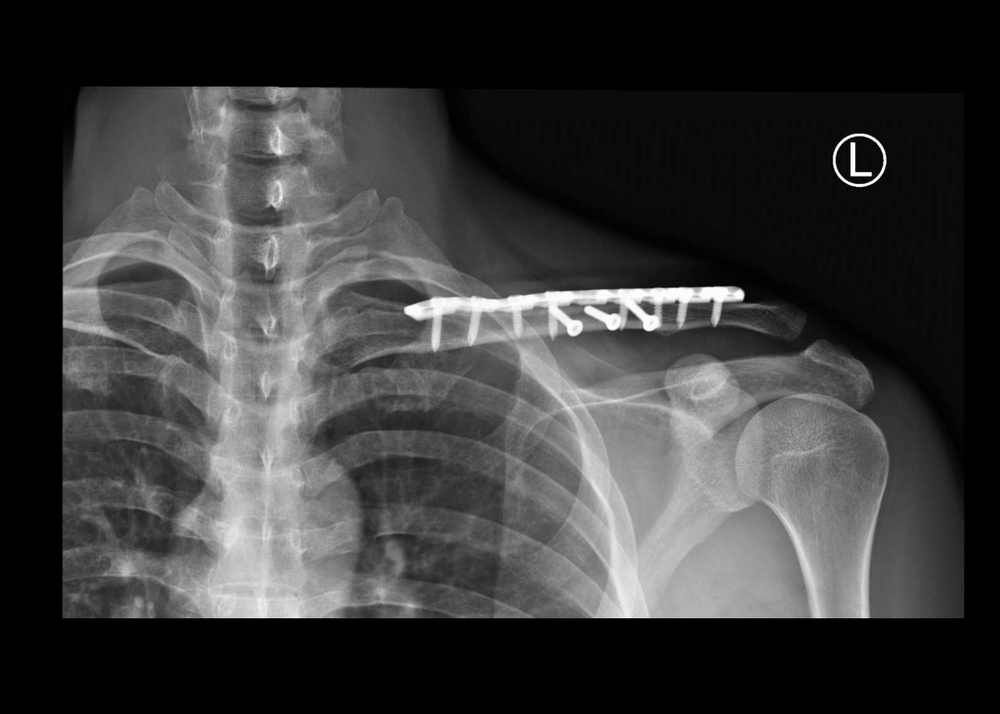

Después de que la anestesia haya sido aplicada, el cirujano hará una pequeña incisión en el hombro a través de la cual introducirá el artroscopio (cámara conectada a un monitor de video).

A continuación el cirujano inspeccionará todos los tejidos de la articulación del hombro y reparará cualquier tejido dañado. Para reparar dicho tejido, podrán hacerse de una a tres incisiones adicionales más pequeñas que la primera, para introducir los instrumentos.

Finalmente el cirujano cerrará las incisiones con suturas y las cubrirá con un vendaje.

Dependiendo del grado de daño en la articulación, es posible que el cirujano requiera realizar una cirugía abierta que le permita llegar directamente a los huesos y tejidos.